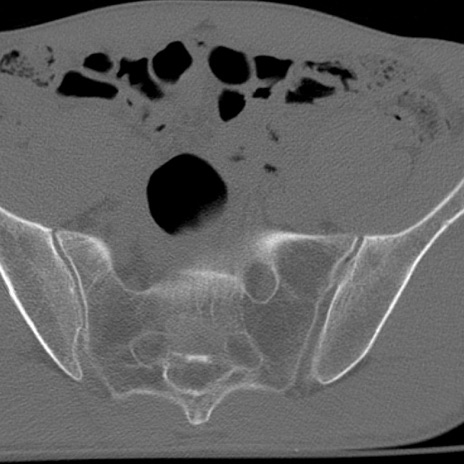

症例3 腰椎CT(横断像)

腰椎CT

冠状断像